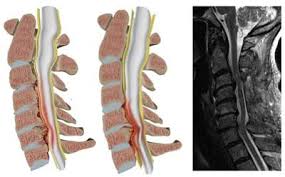

تنگی کانال نخاع

کانال

نخاع فضایی است در داخل ستون فقرات که در داخل آن نخاع قرار گرفته است. این کانال

از کنار هم قرار گرفتن سوراخی که در وسط مهره ها است ایجاد میشود. این کانال از

داخل توسط غشاء محکمی بنام

لیگامان زرد حمایت

میشود.

تنگی کانال نخاع چیست؟

تنگی

کانال نخاع (spinal canal stenosis) یک وضعیت غیر طبیعی است که

میتواند در هر قسمتی از کانال نخاعی اتفاق بیفتد. وقوع این حالت در قسمت کمر بیشتر

از سایر قسمتهای ستون فقرات میباشد. کوچک شدن این فضا سبب فشار روی نخاع در داخل

کانال شده و علائم این بیماری ایجاد میشود.

تشخیص

با مراجعه بیماران به کلینیک درد و معاینه دقیق صورت میگیرد.

شایعترین وسیله تایید این تشخیص انجام MRI

میباشد.